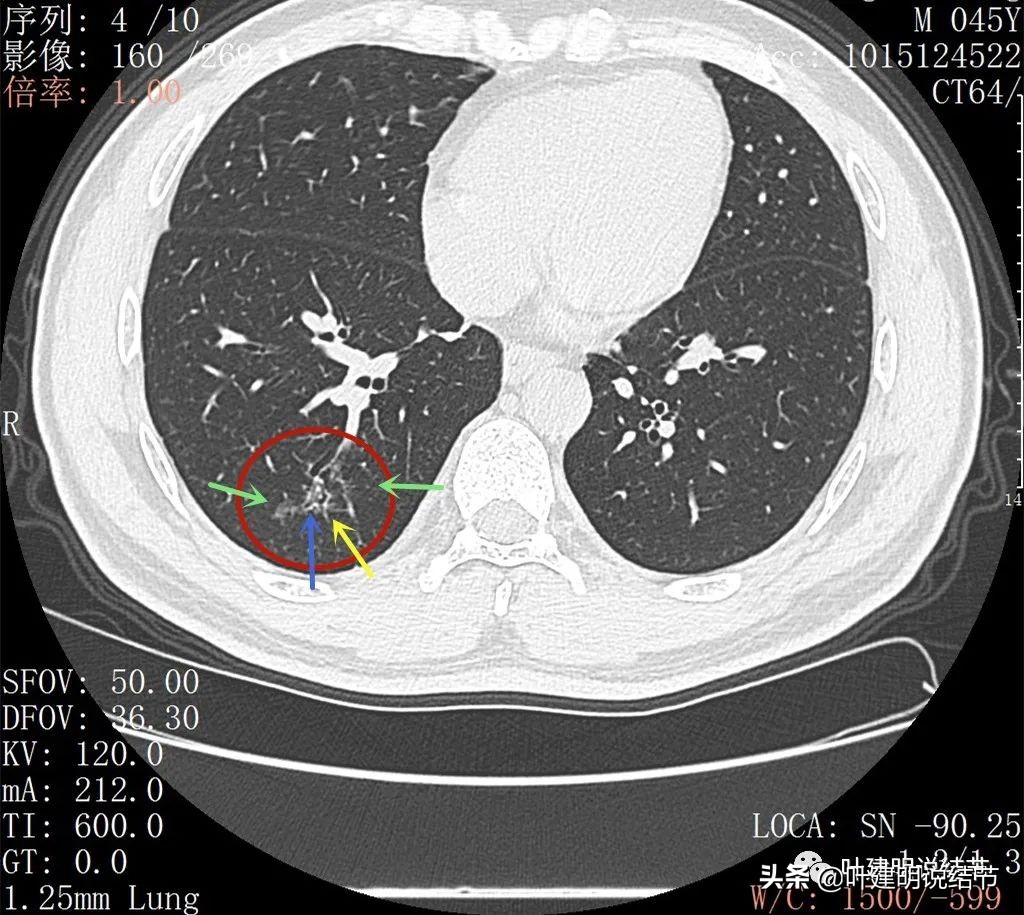

病灶感觉很散在,但内部有扩张的细支气管(黄色箭头)、边缘略显不清(绿色箭头),部分有偏实性(粉色箭头)。

边缘血管异常增粗(桔色箭头),边缘显糊(绿色箭头),细支气管扩张(黄色箭头)

病灶似乎非圆形或类圆形,扩张的细支气管壁密度偏高(蓝色箭头),感觉比较僵硬(黄色箭头),病灶轮廓显模糊(黄色箭头)

右下叶背段有散在斑点状病灶,形态类似,但较主病灶小得多;左侧也有小结节状。

邻近病灶的下叶背段处也有形态类似的病变